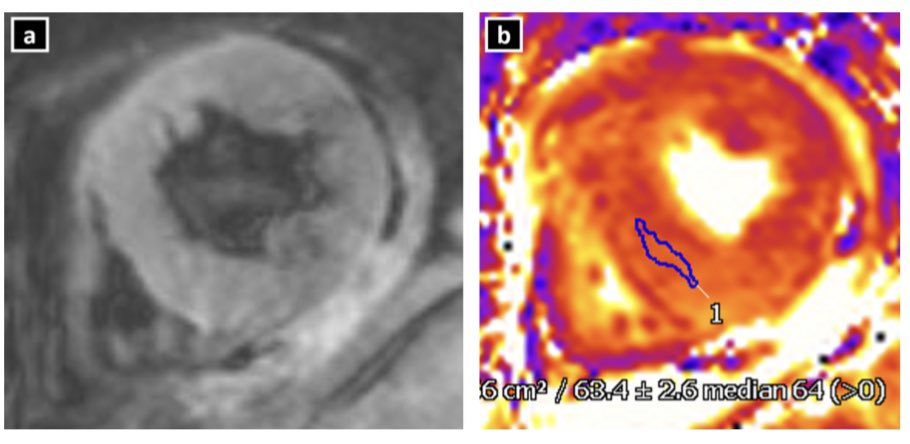

raised T1 and T2 mapping values

raised T1 and T2 mapping values

raised T1 and T2 mapping values

absence of LGE (at +5SD threshold) , but recent studies suggest LGE may be present  T1 and ECV mapping detect diffuse ECM abnormalities- here ECV normal at basal LV, increased at apical LV

T1 and ECV mapping detect diffuse ECM abnormalities- here ECV normal at basal LV, increased at apical LV strain can help detect myocardial deformation abnormalities

absence of LGE (at +5SD threshold) , but recent studies suggest LGE may be present  T1 and ECV mapping detect diffuse ECM abnormalities- here ECV normal at basal LV, increased at apical LV

T1 and ECV mapping detect diffuse ECM abnormalities- here ECV normal at basal LV, increased at apical LV strain can help detect myocardial deformation abnormalities